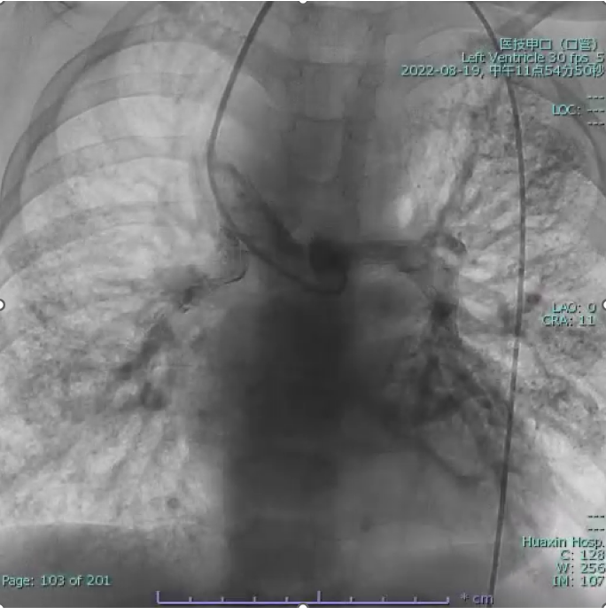

Cardiac catheterization confirmed absence of antegrade pulmonary flow with well-developed bilateral pulmonary arteries. Distal pulmonary arteries and pulmonary venous branches were markedly dilated, some showing a granular or ¡°string-of-beads¡± appearance. Pulmonary circulation time was shortened, indicating significant right-to-left intrapulmonary shunting consistent with diffuse PAVMs. Pulmonary artery pressure was 17/9/13 mmHg.